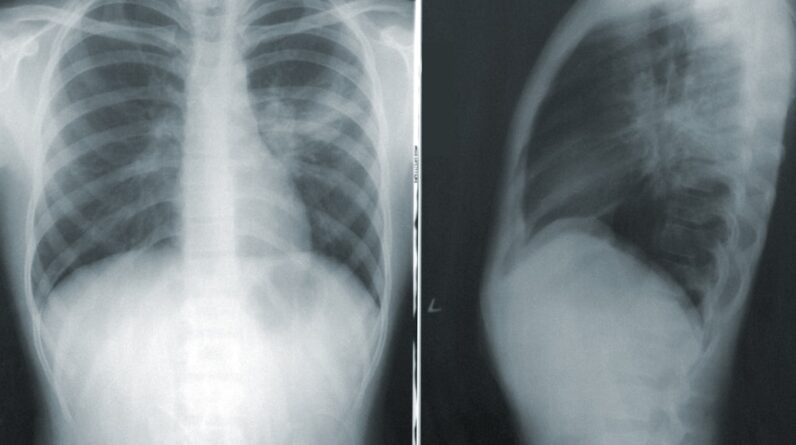

If you have been exposed to asbestos and are experiencing symptoms such as persistent cough, chest pain, or unexplained weight loss, seeking medical attention should be a priority. Early diagnosis is critical for improving treatment outcomes and managing symptoms effectively. Your healthcare provider may recommend imaging tests such as X-rays or CT scans to assess any abnormalities in your lungs or other affected areas.

Asbestos-related cancer is typically diagnosed through a combination of medical history, physical examination, imaging tests (such as X-rays or CT scans), and biopsy. A doctor will also consider any history of asbestos exposure when making a diagnosis.